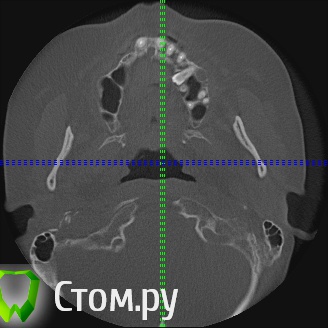

Игорь Пеликан Опубликовано 19 января, 2014 Поделиться Опубликовано 19 января, 2014 Прошу поделиться своими мыслями по поводу хирургической реабилитации(костная пластика) девушки 35 лет,все это покрыто двумя сьемниками.Верх-2 сектор оставляем,в 1 секторе синус,3D.Низ-закапываются сомнения в васкуляризации графта в дистальных отделах, 3D или репозиция,не хочется воспользоваться только междументальным расстоянием? Ссылка на комментарий

Mane Опубликовано 19 января, 2014 Поделиться Опубликовано 19 января, 2014 репозиция нерва. установка имплантатов. далее нерв укладываете латерально. посмотреть бы еще несколько срезов от 36 до 46 Ссылка на комментарий